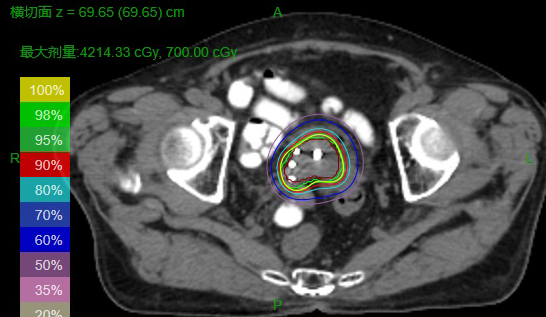

三维适形后装放射治疗通过一定的质量保证手段,留置好施源器后进行CT模拟定位,根据MRI、CT影像勾画出外照射后残留肿瘤及结肠、直肠、膀胱等需要保护的危及器官,利用三维治疗计划系统设计三维适形后装放射治疗计划,可以准确显示出肿瘤的照射剂量、危及器官的受照剂量,达到个体化治疗的目的。

团队有序、合理的协作保证了我院三维适形后装放射治疗技术在疫情防控下的顺利开展。每一次三维适形后装治疗从留置尿管开始到治疗结束,耗时约2-3小时,团队的每一位成员各司其职,无缝衔接,以饱满的工作热情、如饥似渴的学习态度,敬小慎微的作风,脚踏实地完成本职工作。目前,团队已顺利完成子宫颈癌、口底癌、鼻咽癌等8例病人共28次三维适形后装放疗。通过比较,子宫颈癌三维适形后装放疗技术在保证肿瘤得到充分照射的情况下,较传统的二维后装技术更好保护了结肠、直肠和膀胱等危及器官,具有广阔的应用前景。